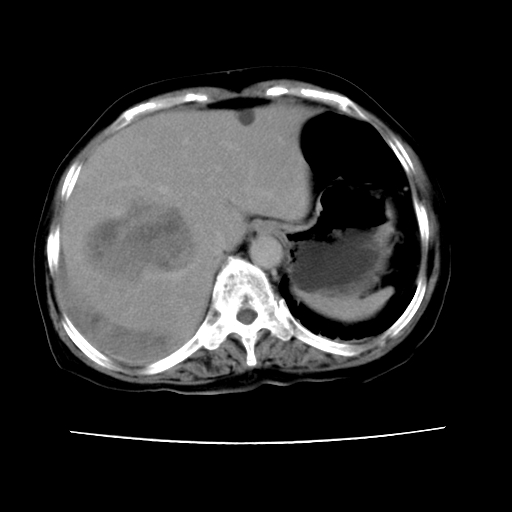

2008-6-10ct平扫

ct增强

6月片:肝血管瘤并破裂出血?肝左外叶囊肿

考虑肝腺瘤出血可能,肝血管瘤增强表现不是很典型,放在第二。

考虑为肝血管瘤破裂出血并肝包膜下血肿;右侧少量胸腔积液。

6月份ct片显示肝内巨大混杂密度团块,伴包膜下积液(内含液液平面),增强多无明显强化。只能考虑肝占位病变,并肝内、血膜下血肿。肝ca并出血多见,而肝血管瘤并破裂出血少见。